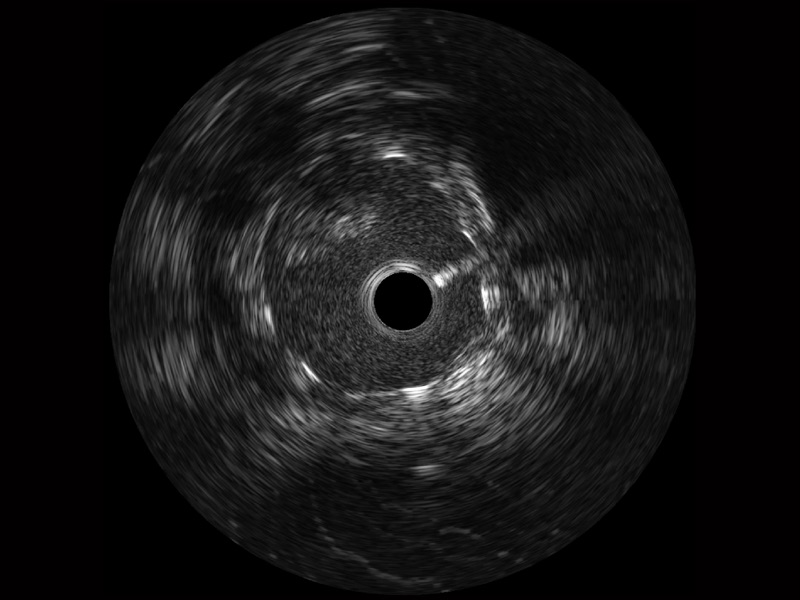

云顶集团官网宽频IVUS图像

传统IVUS图像

对比传统IVUS导管成像,云顶集团官网宽频IVUS图像的近场支架梁显影更细腻,远场中膜外血管仍清晰可辨,兼顾远中近,兼顾分辨力与穿透深度